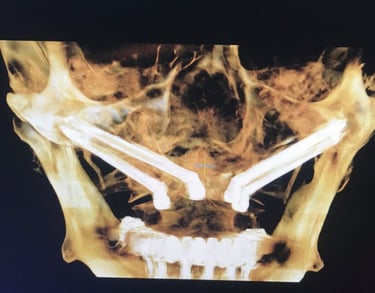

Zdjęcia dzięki uprzejmości prof. Paulo Maló. Prezentacja na forum korporacyjnym sponsorowanym przez Nobel Biocare na dorocznym kongresie Europejskiego Stowarzyszenia na rzecz Osseointegracji, Lizbona, 27 września 2019 r.

Chirurg umieszcza 4 tytanowe implanty w kości szczęki i/lub żuchwy w punktach zaplanowanych wcześniej na podstawie tomografii pacjenta.

IMPLANTY ZYGOMATYCZNE

W przypadku pacjentów z dużym zanikiem kości, optymalnym rozwiązaniem są implanty zygomatyczne (jarzmowe). Implanty jarzmowe różnią się od tradycyjnych implantów dentystycznych tym, że są zamocowane w kości jarzmowej (kości policzkowej), a nie w szczęce. Mają inny, wydłużony kształt i wymagają bardziej złożonej procedury. Jest to wspaniała alternatywa dla pacjentów, która radykalnie skraca czas rekonstrukcji uzębienia i umożliwia pacjentom cierpiącym na ciężką utratę kości szczęki powrót do normalnej jakości życia. W znakomitej ilości przypadków zęby mocuje się już w dniu zabiegu. Tym sposobem pacjent unika wielomiesięcznego cyklu inwazyjnych procedur przeszczepu kości w celu stworzenia podłoża dla konwencjonalnych implantów.

Przed umieszczeniem implantów jarzmowych wykonamy badanie TK, dzięki któremu specjalista implantolog precyzyjnie zaplanuje rozmieszczenie implantów. Następnym krokiem jest stworzenie strukturalnego modelu szczęki (tzw. szablonu), który pozwoli ocenić kształt Twojej kości policzkowej oraz szczęki i dokładnie przeprowadzić operację. Zabieg wszczepienia implantów jarzmowych zazwyczaj odbywa się w głębokim znieczuleniu, więc nie będziesz odczuwać bólu ani dyskomfortu. Nad przebiegiem operacji czuwać będzie zespół wyspecjalizowanych medyków z chirurgiem implantologiem i anestezjologiem na czele.